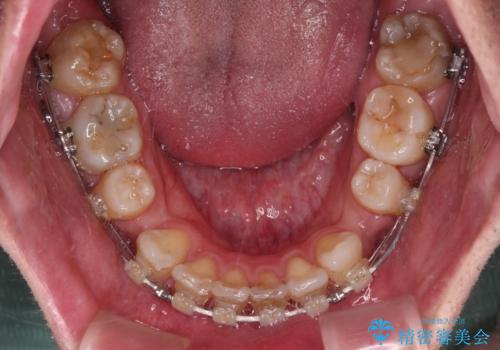

顎が左右にずれた咬み合わせ ハーフリンガルの抜歯矯正

目立たない装置を希望され、上顎が裏側装置で下顎が表側装置のハーフリンガルを希望されました。

上下の顎骨が左右に大きくずれており、奥歯が交叉咬合となっていたため、ハーフリンガルよりも表側装置をおすすめしましたが、目立たない装置を強く希望されたため、治療期間が長期化することを前提に、ハーフリンガルにて抜歯矯正を行うこととしました。

裏側装置での交叉咬合改善は非常に困難なもので、頻繁に装置の脱落がありました。

それでも想定以上に治療期間は長期化せず、咬み合わせも口元も満足のいく仕上がりとなりました。